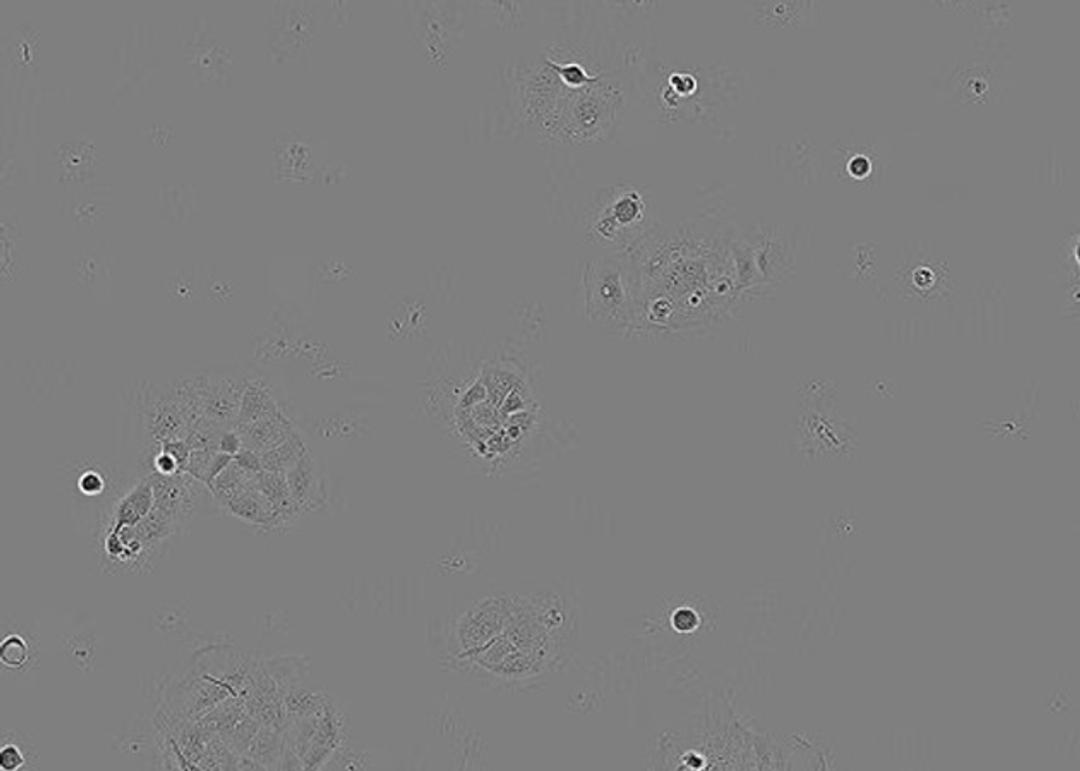

CACO-2 Cell Line human

The CACO-2 cell line is a widely used in vitro model for mimicking the small intestine for drug transport studies. These cell lines form monolayers and are useful in intestinal permeation studies for screening excipients in drug formulations.